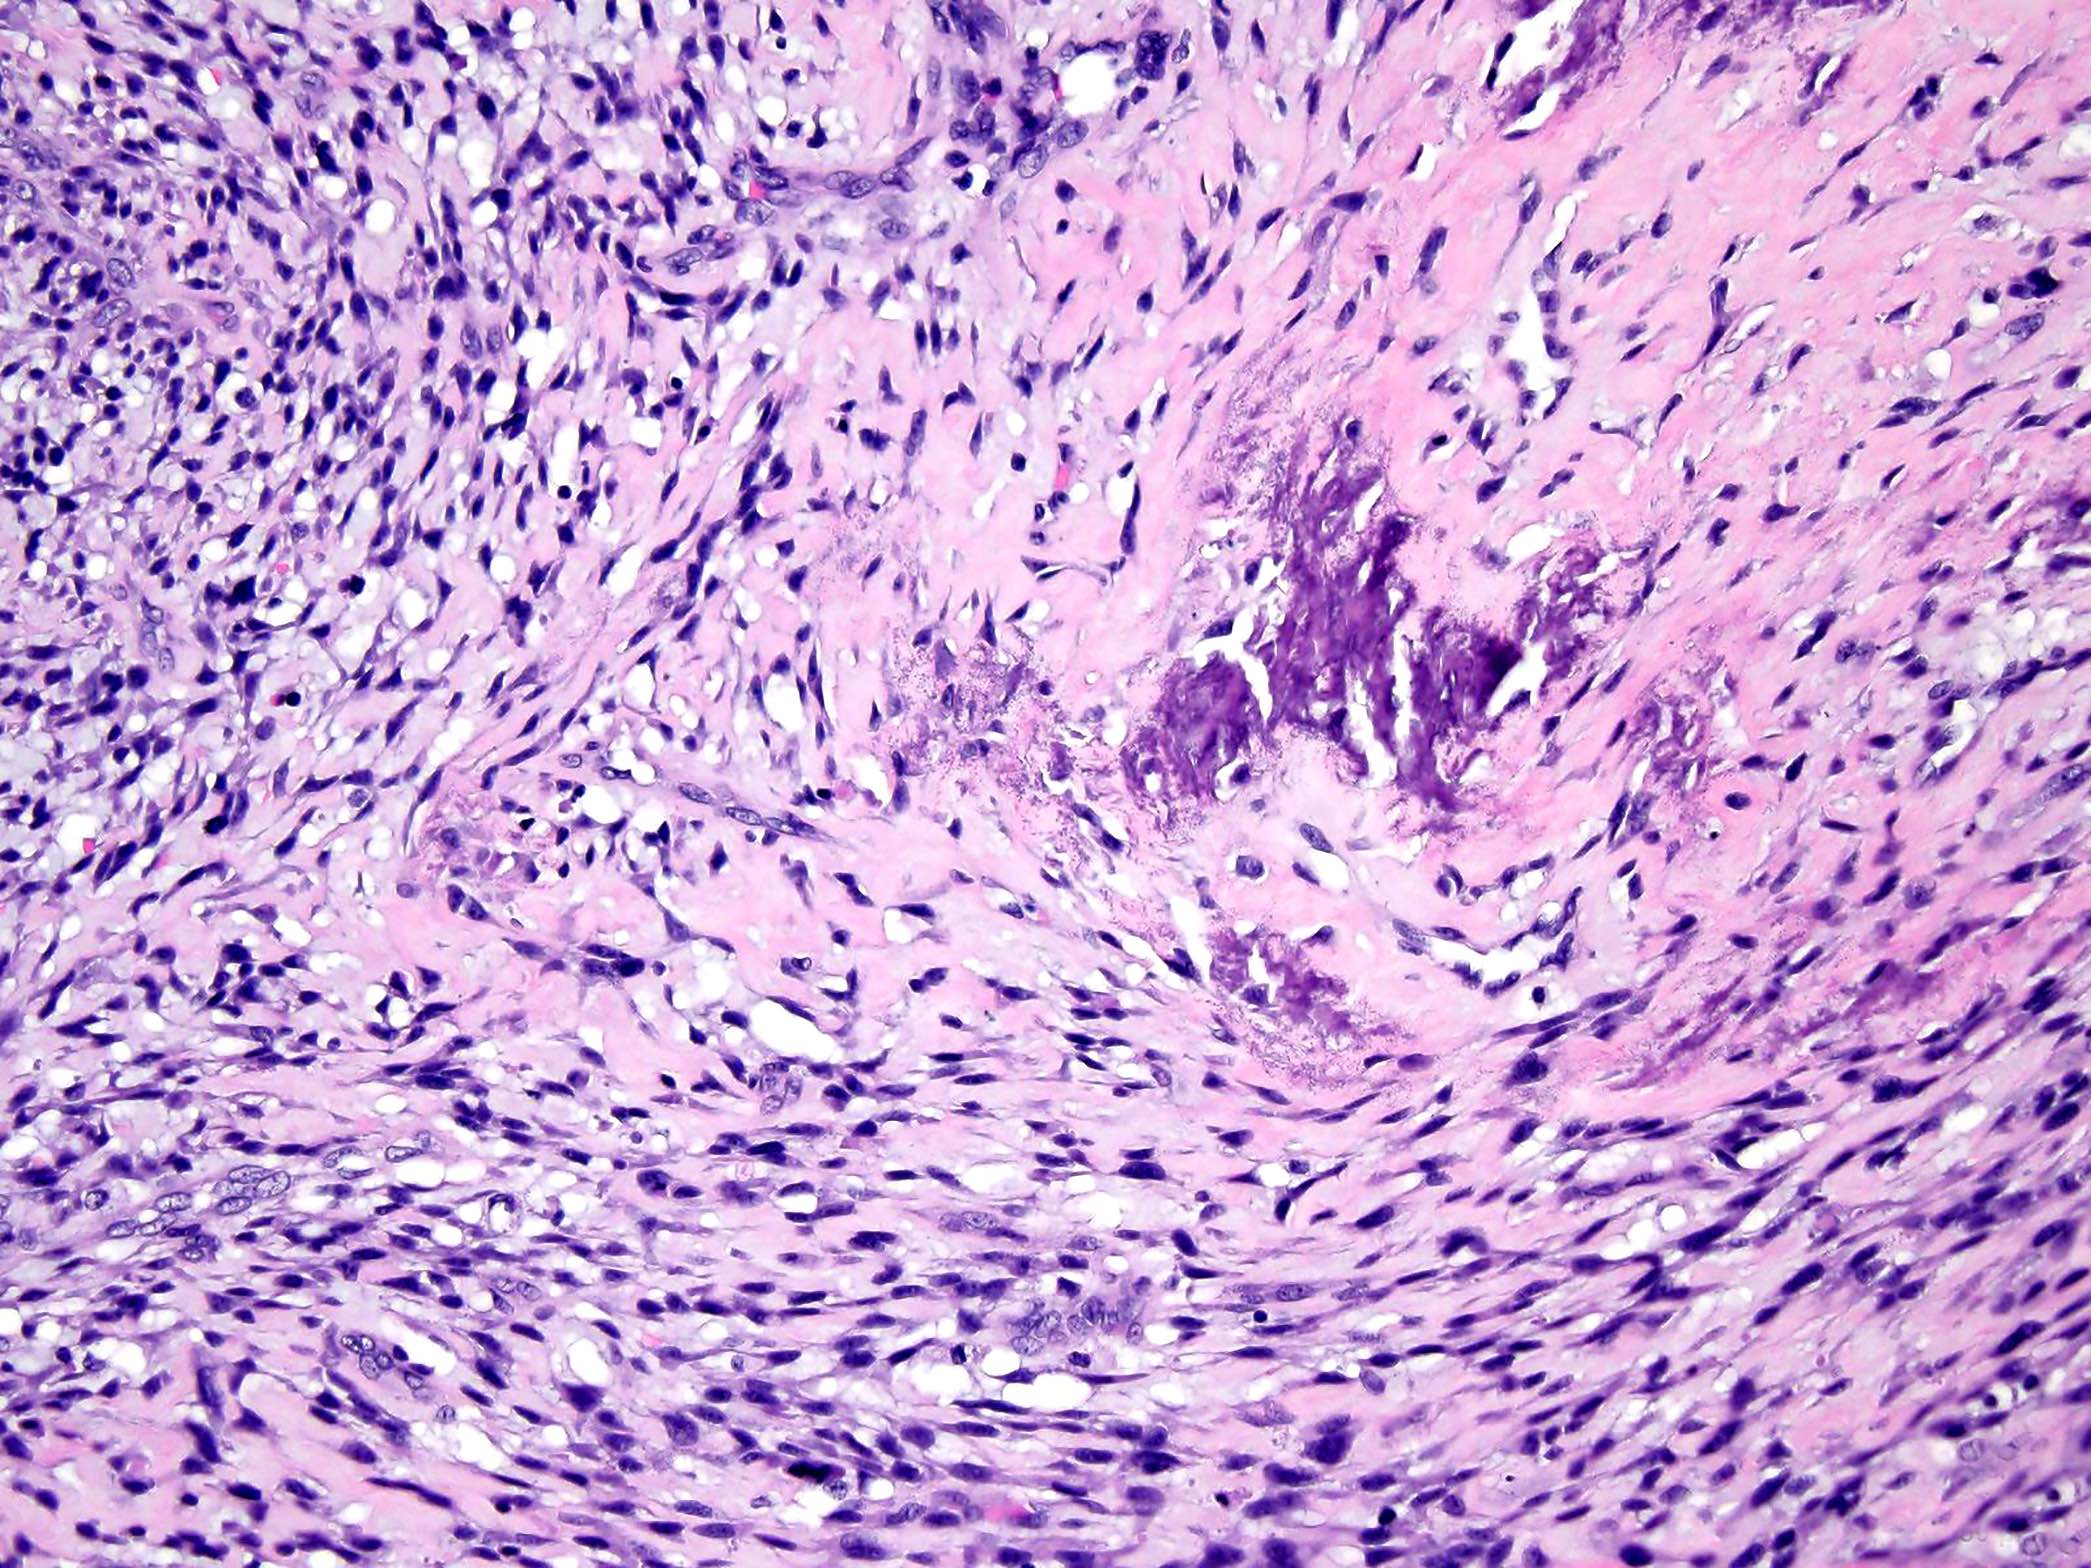

Microscopic (histologic) images

Contributed by Jesse Hart, D.O., Borislav A. Alexiev, M.D. and AFIP

- Low grade central osteosarcoma:

- Permeative growth:

- Intramedullary (surrounds and erodes native trabeculae, fills Haversian systems)

- Cortical destruction and soft tissue invasion

- Neoplastic cells: fibroblast-like spindle cells (minimal atypia); hypocellular to moderately cellular

- Scattered mitoses may be seen

- Rare, scattered higher grade areas may be present

- Arranged in fascicles or interlacing bundles

- Neoplastic bone:

- Bone trabeculae (fibrous dysplasia-like): curved, branching or interanastomosing

- Longitudinal lamellar bone: like parosteal osteosarcoma

- Benign multinucleated giant cells: present in 33% of cases

- With or without scattered foci of atypical cartilage

- Dedifferentiation / high grade transformation (10 - 35% of cases):

- High grade osteosarcoma

- High grade undifferentiated pleomorphic sarcoma

- Fibrosarcoma

- Most common in recurrent tumors (2 - 3 years after resection) but may be seen in the primary tumor

- Permeative growth:

A 12 year old girl has a 10.5 cm intramedullary mass in the distal femur, which was resected (see gross and microscopic images). High power views demonstrate bland spindle cells. Which of the following is most accurate regarding this tumor?

Practice answer #1

A. Most likely, genetic abnormality is amplification of the MDM2 gene. The tumor is a low grade central osteosarcoma.